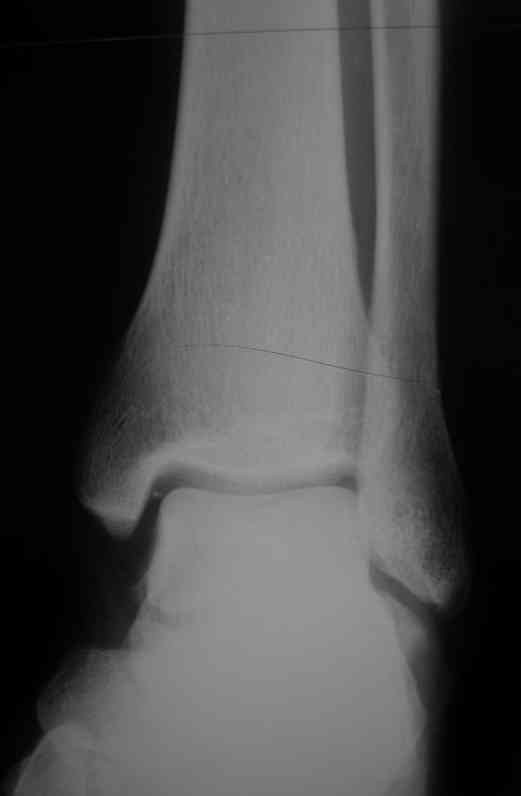

Уважаемые коллеги. Хотелось бы услышать ваше мнение по следующему случаю Обратился больной 23 года, травма 4 месяца назад - закрытый перелом наружной, внутренней лодыжки правой голени. Лечился консервативно, гипсовой иммобилизацией 8 недель, после снятия последней прошел курс восстановительного лечения. Беспокоят боли в области правого голеностопного сустава больше в проекции внутренней лодыжки, к вечеру. Отечность области сустава при физических нагрузках.Походка не изменена. Контуры правого голеностопного сустава сглажены. Имеется вальгусная установка правой пяточной кости. Объем движений в голеностопном суставе подошвенное / тыльное сгибание 50/0/80, безболезненные. Посоветуйте что делать в данной ситуации. Мне видится следующий вариант решения данной деформации: Восстановление нормальной анатомии голеностопного сустава - остеотомия малоберцовой кости и внутренней лодыжки, удалить все рубцы из области дистального межберцового синдесмоза, восстановить длину и устранить ротационное смещения наружной лодыжки.( встанет ли таранная кость на место?), фиксация наружной лодыжки пластиной, внутренней - винтами, дистального межберцового синдесмоза винтом. ЭОПом не располагаем. Что вы посоветуете? Где могут быть - технические трудности, <подводные камни>.

P.S. На боковой проекции таран выглядит несимпатично. Может быть изза качества снимка?

> подошвенное / тыльное сгибание 50/0/80

От 0 в одну сторону 50 градусов, и в другую 80? То есть амплитуда 130 градусов?